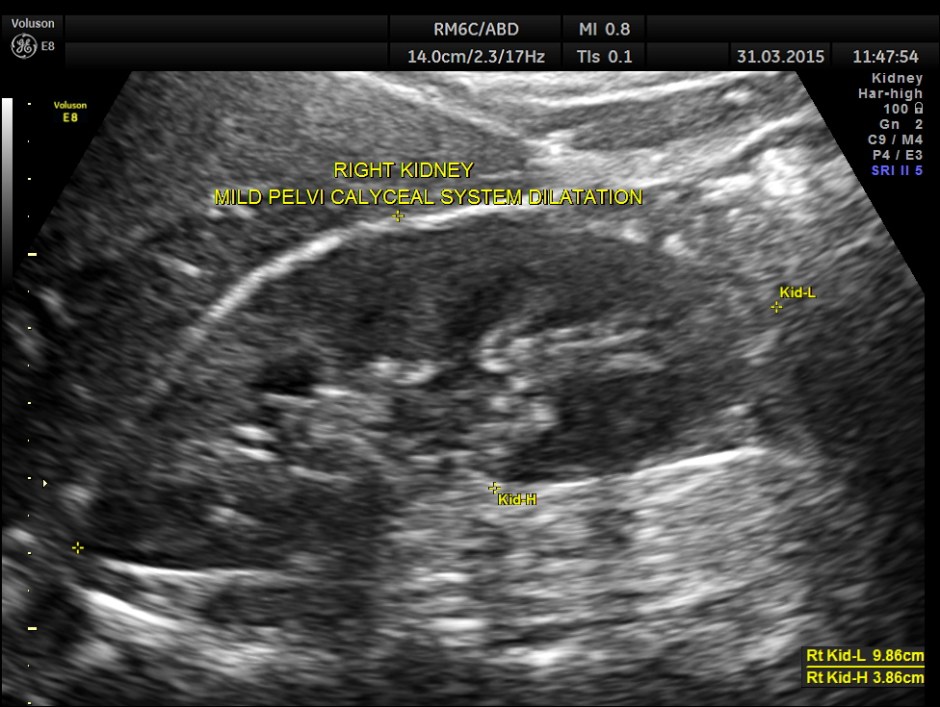

Ultrasound showed the following.

Right kidney shows mild pelvi calyceal dilatation.

Is there an incongruity between the size of the calculus and the ” ureteric dilatation ” and the pelvi calyceal dilatation ?